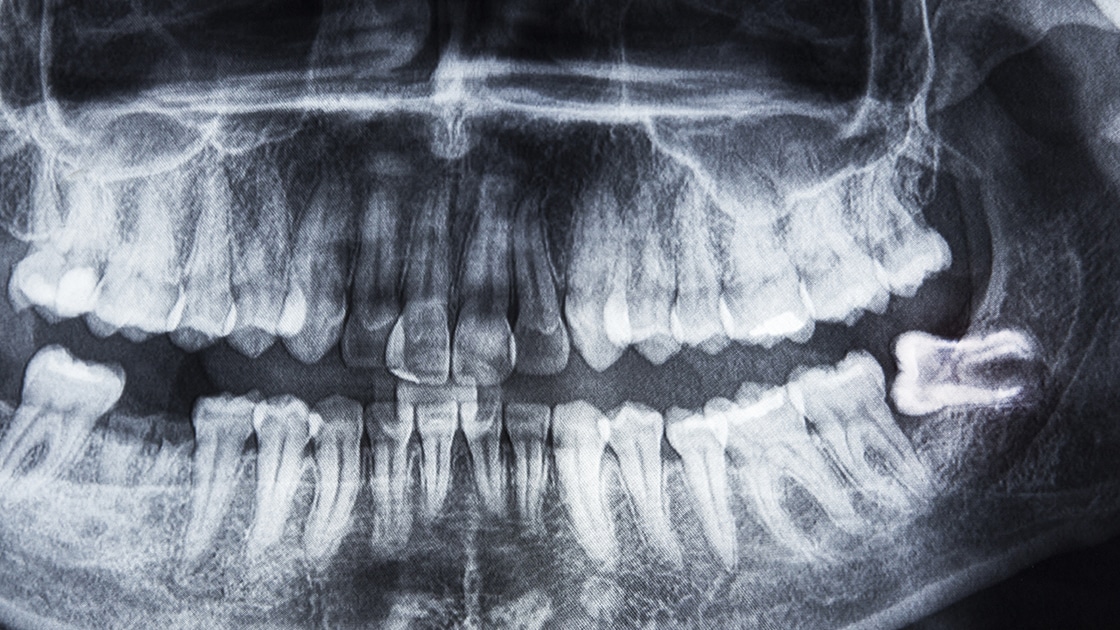

Wisdom teeth, or third molars, are removed only if they are deemed potentially problematic. There are several reasons a wisdom tooth might be labeled as problematic. Factors that determine whether or not wisdom teeth must be removed include jaw size, crowding, proper occlusion, and impaction. Often, radiographs taken at regular dental cleaning appointments will show when wisdom teeth extraction is recommended.

An impacted tooth is one that is blocked from erupting. Impacted wisdom teeth that are blocked from coming in properly:

May instead come in at an angle, pushing against the molars and causing overcrowding.

May not erupt fully, remaining instead either partially or fully below the gum line.